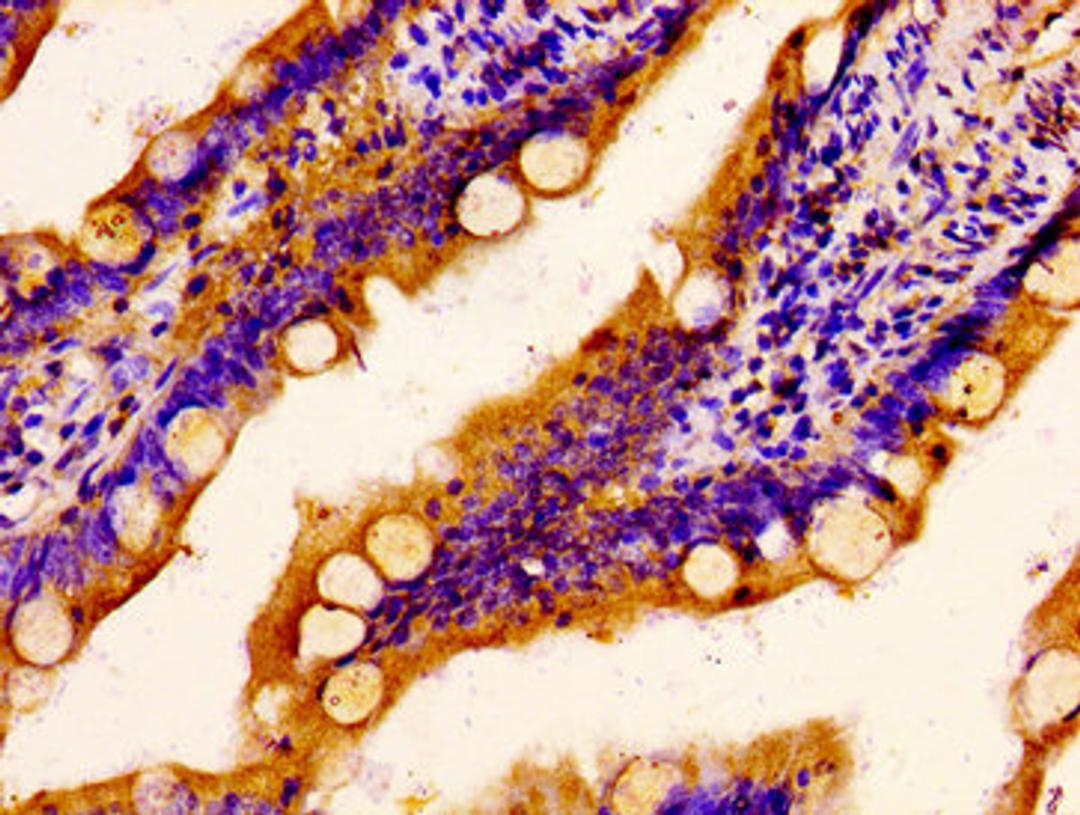

IHC image of CSB-PA020766LA01HU diluted at 1:400 and staining in paraffin-embedded human small intestine tissue performed on a Leica BondTM system. After dewaxing and hydration, antigen retrieval was mediated by high pressure in a citrate buffer (pH 6.0). Section was blocked with 10% normal goat serum 30min at RT. Then primary antibody (1% BSA) was incubated at 4°C overnight. The primary is detected by a biotinylated secondary antibody and visualized using an HRP conjugated SP system.